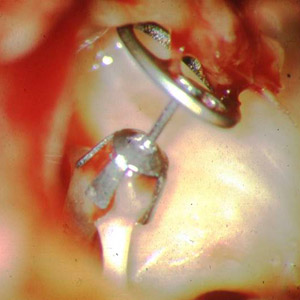

Tympanoplastik Typ 3a mit einer Titan-Partial-Prothese wird die Verbindung zwischen Trommelfell und Steigbügelköpchen hergestellt.